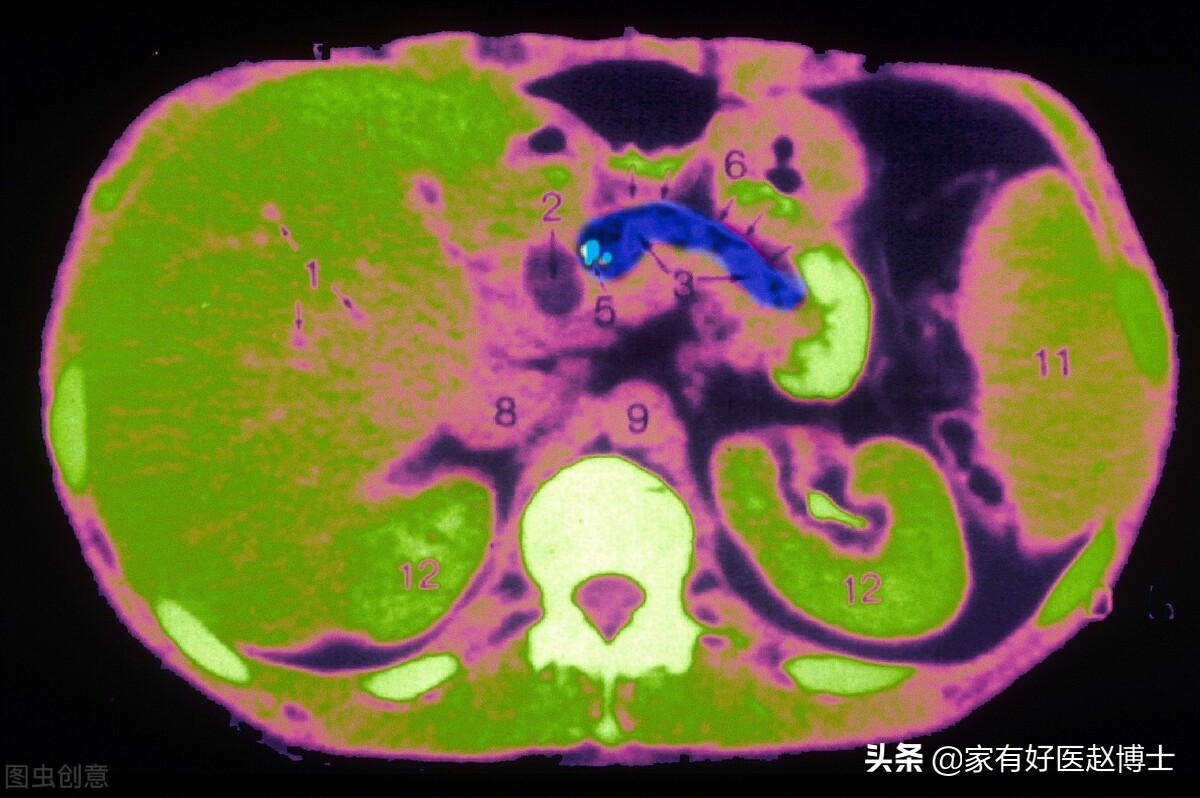

钙化可以说是无处不在,人体的很多重要器官里都可以检测出钙化,比如肝脏、肺、甲状腺、乳腺、前列腺等。而除了具体的器官以外,遍布全身的血管壁上也可以发现钙化。

动脉钙化=动脉硬化

前面我们说到的,主要是一些重要器官当中出现的钙化,而还有一类钙化也在体检中常常遇到,这就是血管的钙化。有时候,肺部CT扫描可以看到主动脉或冠状动脉上的钙化,而颈动脉超声检查则可以识别出颈动脉内膜中的钙化。

动脉钙化与器官中的钙化不同,它并不会提示癌症风险,但是,它却常常意味着另一项足以致命的危险,这就是动脉硬化。大家需要记住很重要的一点,这就是:存在动脉钙化就等于存在动脉硬化。

因此,如果在体检中发现了动脉钙化,请仔细回忆一下:自己的血压、血糖、血脂等重要心血管指标是否都正常,如果存在异常,那应该尽早开始进行干预和治疗;哪怕这些指标都正常,那说明年龄和衰老这项单一因素已经导致了心血管系统的退化,要充分意识到自己正在面临不断增大的心血管风险。